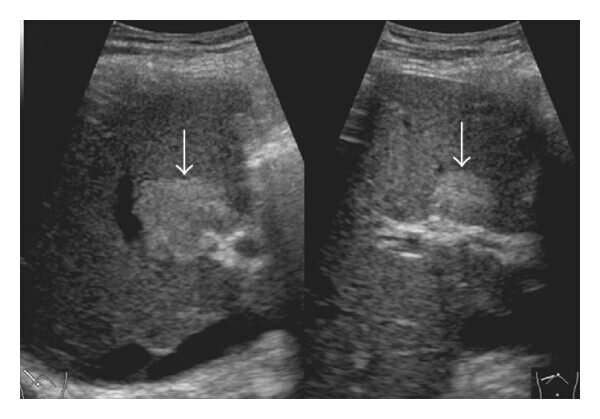

# Abdome: doença hepática difusa HD?

Pericardite com hepatopatia congestiva (crônica). ## Footnote Padrão heterogêneo, mosqueado, reticulado e em mosaico do parênquima hepático (fígado em noz-moscada) e presença de nódulos regenerativos e ascite.

# Abdome: doença hepática difusa **Hepatopatia congestiva** Fisiopatologia?

Drenagem venosa prejudicada ➔ estase sanguínea no parênquima hepático (VCI e veias hepáticas dilatadas)

# Abdome: doença hepática difusa **Hepatopatia congestiva** Achados típicos TC? (4)

1. Realce retrógrado precoce da veia cava inferior (VCI) dilatada e das veias hepáticas (VHs); 2. Padrão heterogêneo, mosqueado, reticulado e em mosaico do parênquima hepático (fígado em noz-moscada); 3. Baixa atenuação periportal (linfedema perivascular); 4. Hepatomegalia e ascite.